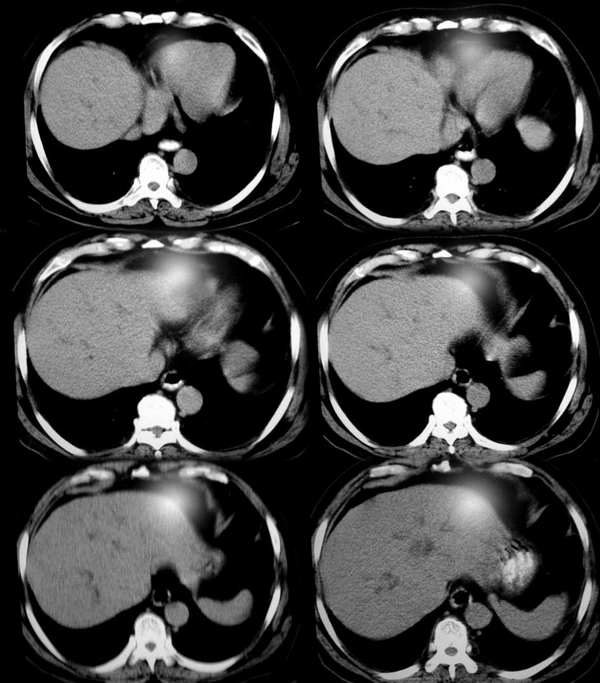

标题: CT2418:求诊:无痛性黄疸10天,无发热。

男,70y,就是单纯无痛性黄疸

胆囊不扩大,较小,壁增厚,其内见小斑点状结石灶。肝内胆管扩张,扩张至肝门区,其内侧见小斑状高密度影,以下胆管无明显扩大。考虑1肝内胆管扩大,考虑肝门部占位.2胆囊炎胆结石。建议增强检查。

肝脏体积不大,肝裂稍宽,肝实质密度均匀,肝内胆管呈枯枝状扩张,在肝门区突然中断,胆总管未见明显增宽,胆囊缩小,壁厚并见斑点状钙化。考虑:1)肝外远侧段肝总管癌,2)慢性胆囊炎。(若能提供年龄、增强片子更好)

肝脏体积不大,肝裂稍宽,肝实质密度均匀,肝内胆管呈枯枝状扩张,在肝门区突然中断,胆总管未见明显增宽,胆囊缩小,壁厚其内侧见小斑状高密度影,考虑1肝内胆管扩大,考虑;1肝门部占位.2胆囊炎胆结石。

肝脏形态不规则,肝裂较宽,尾叶增大;胆囊较小,壁厚,其内可见不规则高密度影;于肝门区见胆总管扩张;胰腺形态密度无著变,羽毛征存在,腹腔内未见明显肿大淋巴结。余(—)

印诊:1、低位胆道梗阻,胆总管扩张,肝内胆管扩张,不除外炎症所致,建议治疗后复查,排除胆总管占位(有条件可以做ercp或ct增强);2、肝硬化;3、胆囊炎,胆囊结石。

肝体积不大,肝裂宽,肝密度均匀,肝内胆管扩张,胆总管突然截断,管壁不规则,管腔呈梅花状,考虑 1)胆总管癌 2)胆囊结石,胆囊炎.